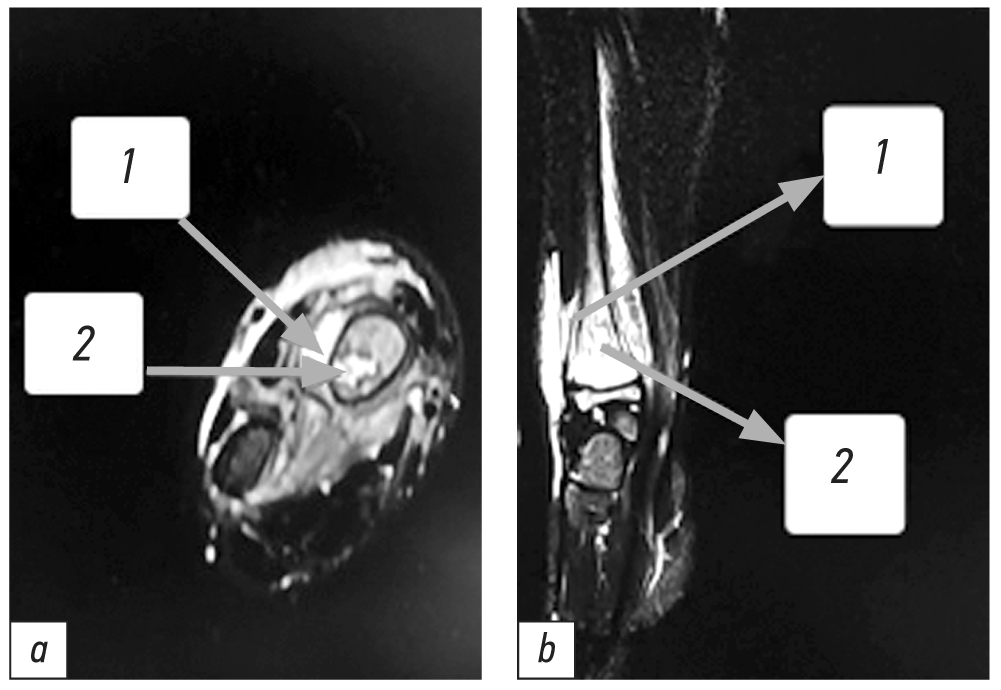

МРТ было выполнено 3 (14,3 %) пациентам, у которых ОГО подтвердился, и они в дальнейшем были оперированы. У девочки 8 лет на 2 сут болезни были выявлены признаки ОГО правой малоберцовой кости в виде зоны снижения интенсивности Т2 сигнала от костного мозга дистальной трети метафиза за счёт ограниченных воспалительных изменений трабекулярной структуры, без видимых секвестральных фрагментов, от которой определяется жидкостное прилегающее содержимое с переходом на субфасциальный отдел (рис. 2).

Рис. 2. Магнитно-резонансная томография малоберцовой кости (девочка 8 лет с острым гематогенным остеомиелитом, 2 сут заболевания, фронтальная плоскость, Т2-взвешенное изображение): зона снижения интенсивности Т2-сигнала от костного мозга дистальной трети метафиза.

Fig. 2. MRI of the fibula (front plane, T2-weighted imaging); patient — girl 8 y.o. with acute hematogenous osteomyelitis on day 2 of the disease; zone of reduced intensity of T2 signal from the bone marrow of the distal third of the metaphysis.

Интраоперационно надкостница свободно отслаивается в нижней трети, кость мягкая, в костномозговом канале получена кровь под давлением. В бактериологическом посеве выявлен S. aureus в титре 105 КОЕ/мл.

У мальчика 13 лет на 5 день болезни были выявлены достоверные признаки ОГО правой лучевой кости в виде выраженной воспалительной реакции и отслоением надкостницы протяжённостью до 4,3 см, наличие участка деструкции в метафизе по медиальной поверхности лучевой кости гипоинтенсивного характера, на Т1 — гиперинтенсивного характера с гипоинтенсивным перифокальным ободком и неоднородными включениями. В метафизе имеется полость формирующегося секвестра размерами 1,75×0,41×0,8 см, переходящая в веретенообразную гиперинтенсивную тень размерами 2,4×0,5×1,25 см — поднадкостничный абсцесс со свищевым ходом 0,6×0,14 см (рис. 3).

Рис. 3. Магнитно-резонансная томография лучевой кости (мальчик 13 лет, 5 день заболевания, Т2-взвешенное изображение с жироподавлением, a — горизонтальная плоскость, b — фронтальная плоскость): 1 — выраженная воспалительная реакция и отслоение надкостницы, 2 — гипоинтенсивный участок деструкции в метафизе по медиальной поверхности лучевой кости.

Fig. 3. MRI of the radial bone (T2-weighted imaging with suppression of MR signal from adipose tissue) on day 5 of the disease; patient is a 13-year-old boy, a — axial plane, b — coronary plane): 1 — pronounced inflammatory reaction of the periosteum and its detachment, 2 — hypointensive metaphysis destruction zone along the medial surface of the radial bone.